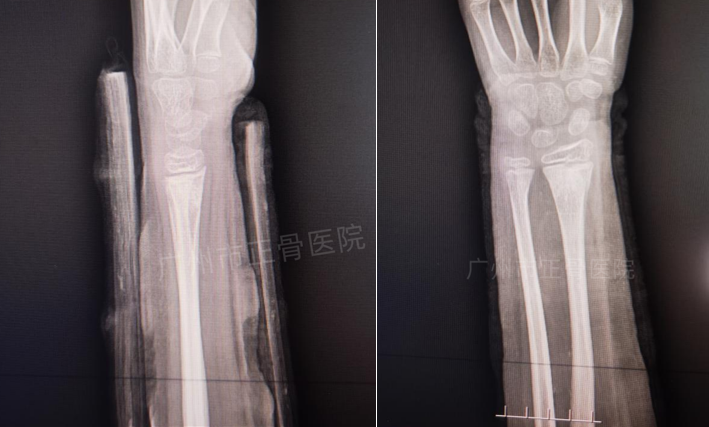

治疗:根据院桡骨远端骨折诊疗规范,予手法复位夹板外固定治疗。复位后复查X片提示骨折对位对线良好,下尺桡关节已复位,外侧加石膏托以加强固定效果,预防移位。嘱患者定期复诊换药(每周一次),指导患者适当功能锻炼。2周后复查X线提示骨折稳定,骨折线稍模糊。6周复查X线提示骨折端位线良好,骨折线已模糊,予拆除夹板,指导患者功能康复锻炼。7周后复诊,提示功能恢复正常。

▲6周后,骨折线模糊,拆除夹板